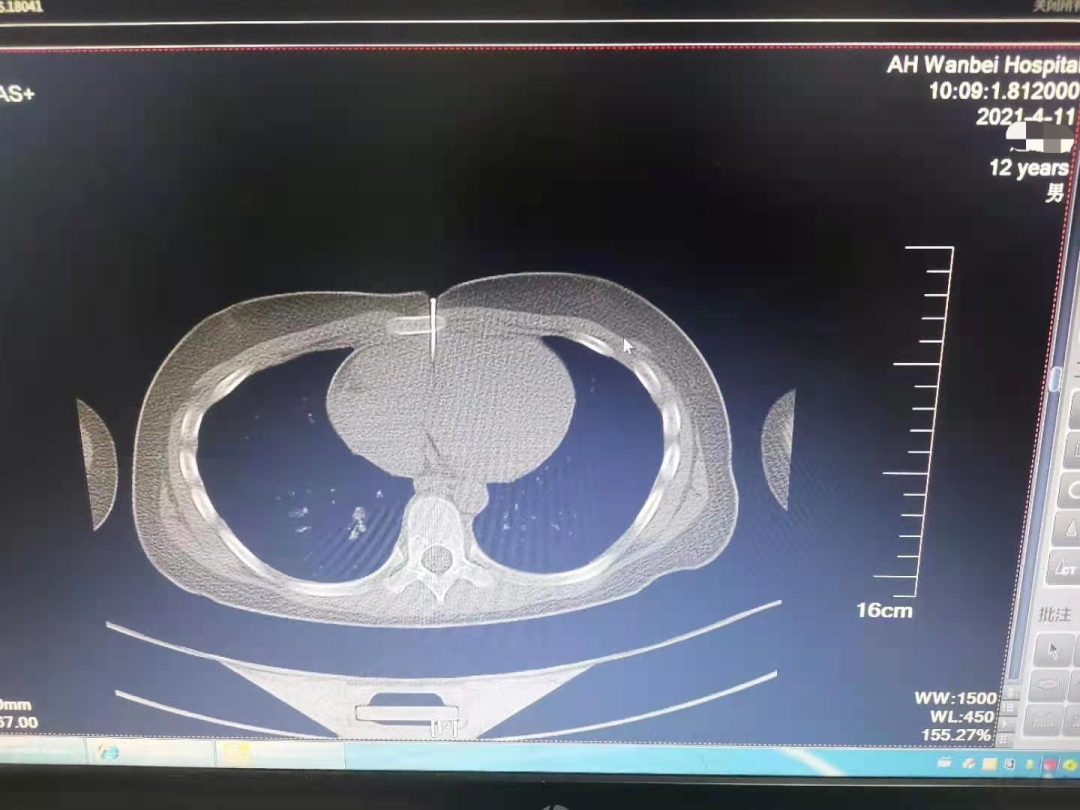

安徽一男童误将气钉枪当玩具 钉子穿透胸骨直达心脏 凤凰网安徽_凤凰

图片尺寸1080x810